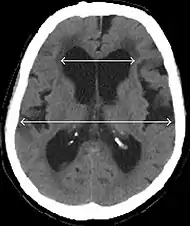

Evan's index is the ratio of maximum width of the frontal horns to the maximum width of the inner table of the cranium. An Evan's index more than 0.31 indicates hydrocephalus.[8]

Typical imaging findings in normal pressure hydrocephalus versus brain atrophy.[9]

Normal pressure hydrocephalusBrain atrophy

Preferable projectionCoronal plane at the level of the posterior commissure of the brain.

Modality in this exampleCTMRI

CSF spaces over the convexity near the vertex (red ellipse )Narrowed convexity ("tight convexity") as well as medial cisternsWidened vertex (red arrow) and medial cisterns (green arrow)

Callosal angle (blue V)Acute angleObtuse angle

Most likely cause of leucoaraiosis (periventricular signal alterations, blue arrows ) Transependymal cerebrospinal fluid diapedesis Vascular encephalopathy, in this case suggested by unilateral occurrence